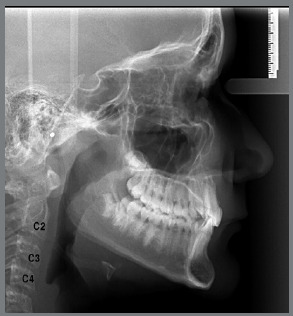

Material and methods: A total of 148 lateral cephalograms (78 males, 70 females) of Class II malocclusion patients, and 60 lateral cephalograms (30 males, 30 females) of normal occlusion patients were included. The following linear cephalometric measurements were performed: Co-Gn (effective mandibular length), Co-Go (ramus height), and Go-Gn (length of mandibular body). Mean values of increments between stages (I-A, A-T, I-T) were obtained for each group and gender. Results were compared using the Student t-test, and a significance level of 0.05% was adopted.

Abstract Image